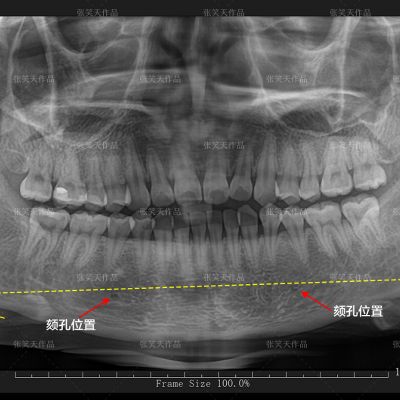

其中,头颅的三维CT对手术方案有指导性意义。口腔的全景片可以看到下颌角的形态和角度,可以看到颏孔的位置和神经线的高低,也可以看到两侧下颌角的对称情况,有部分求美者颏神经线位置过低,可以截出的骨量小,改变的意义不大就没必要手术。